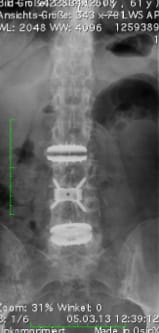

Scoliosis of the lumbar spine, dynamic correction with a cage and two viscoelastic disc prostheses. Even three years after the operation (right image), the spinal axis remains in ideal condition.